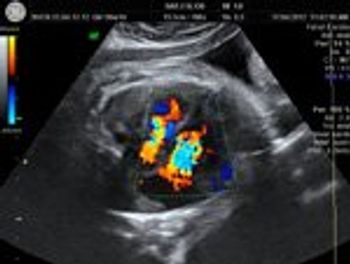

Several recent studies have shown that the addition of secondary ultrasound markers to the combined first-trimester screening for aneuploidies, or chromosomal abnormalities such as trisomy 21 (Down syndrome) and trisomy 18 (Edwards syndrome), can slightly improve screening accuracy.